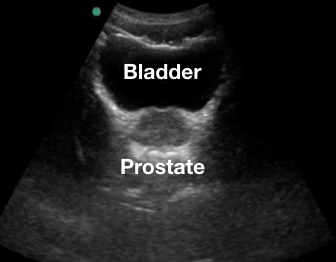

Pelvis

Liquide libre abdominal